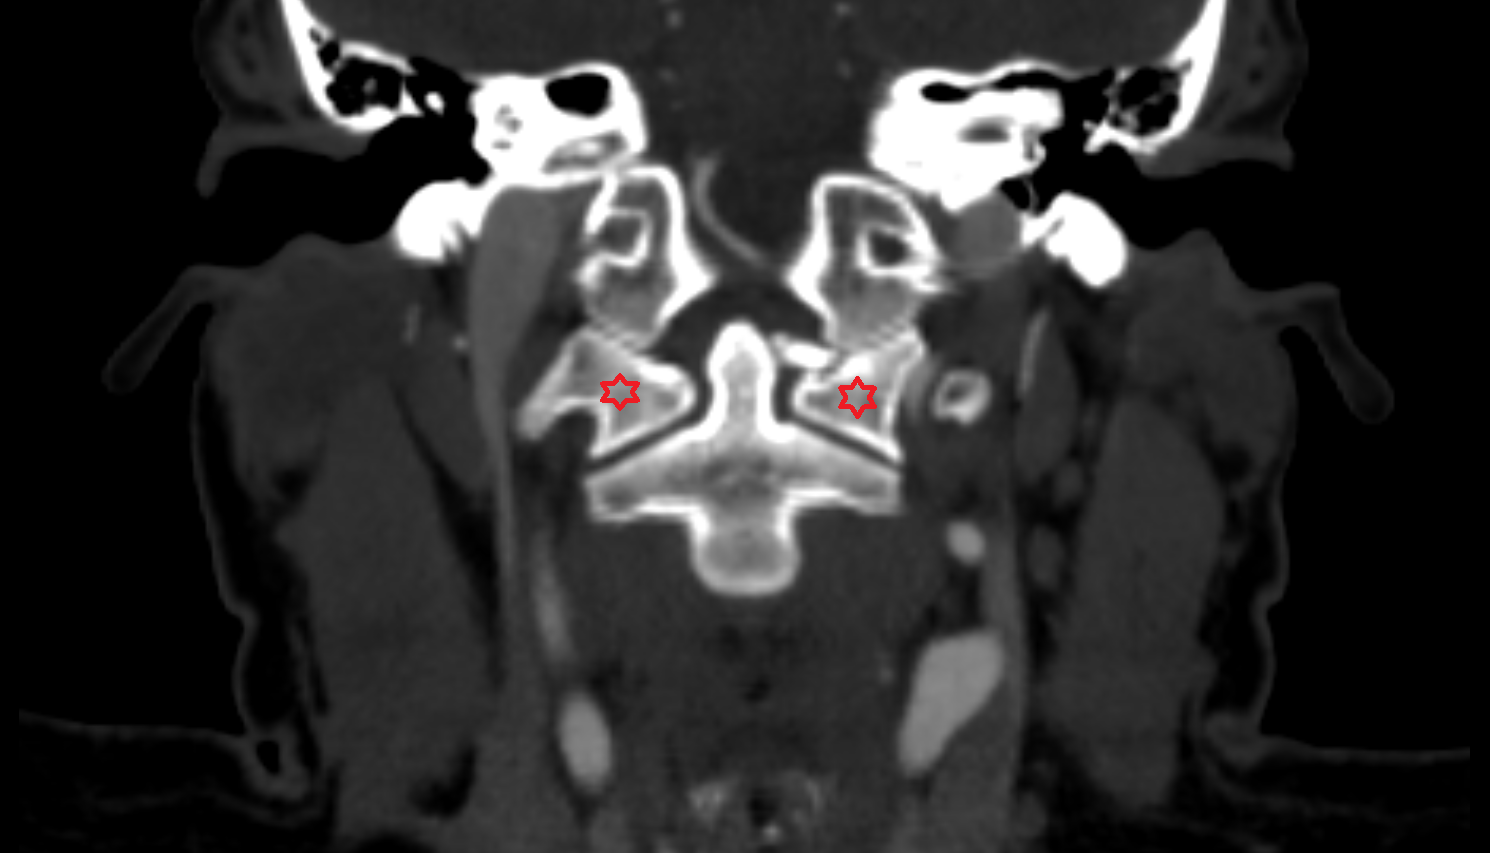

- Maxillary sinus